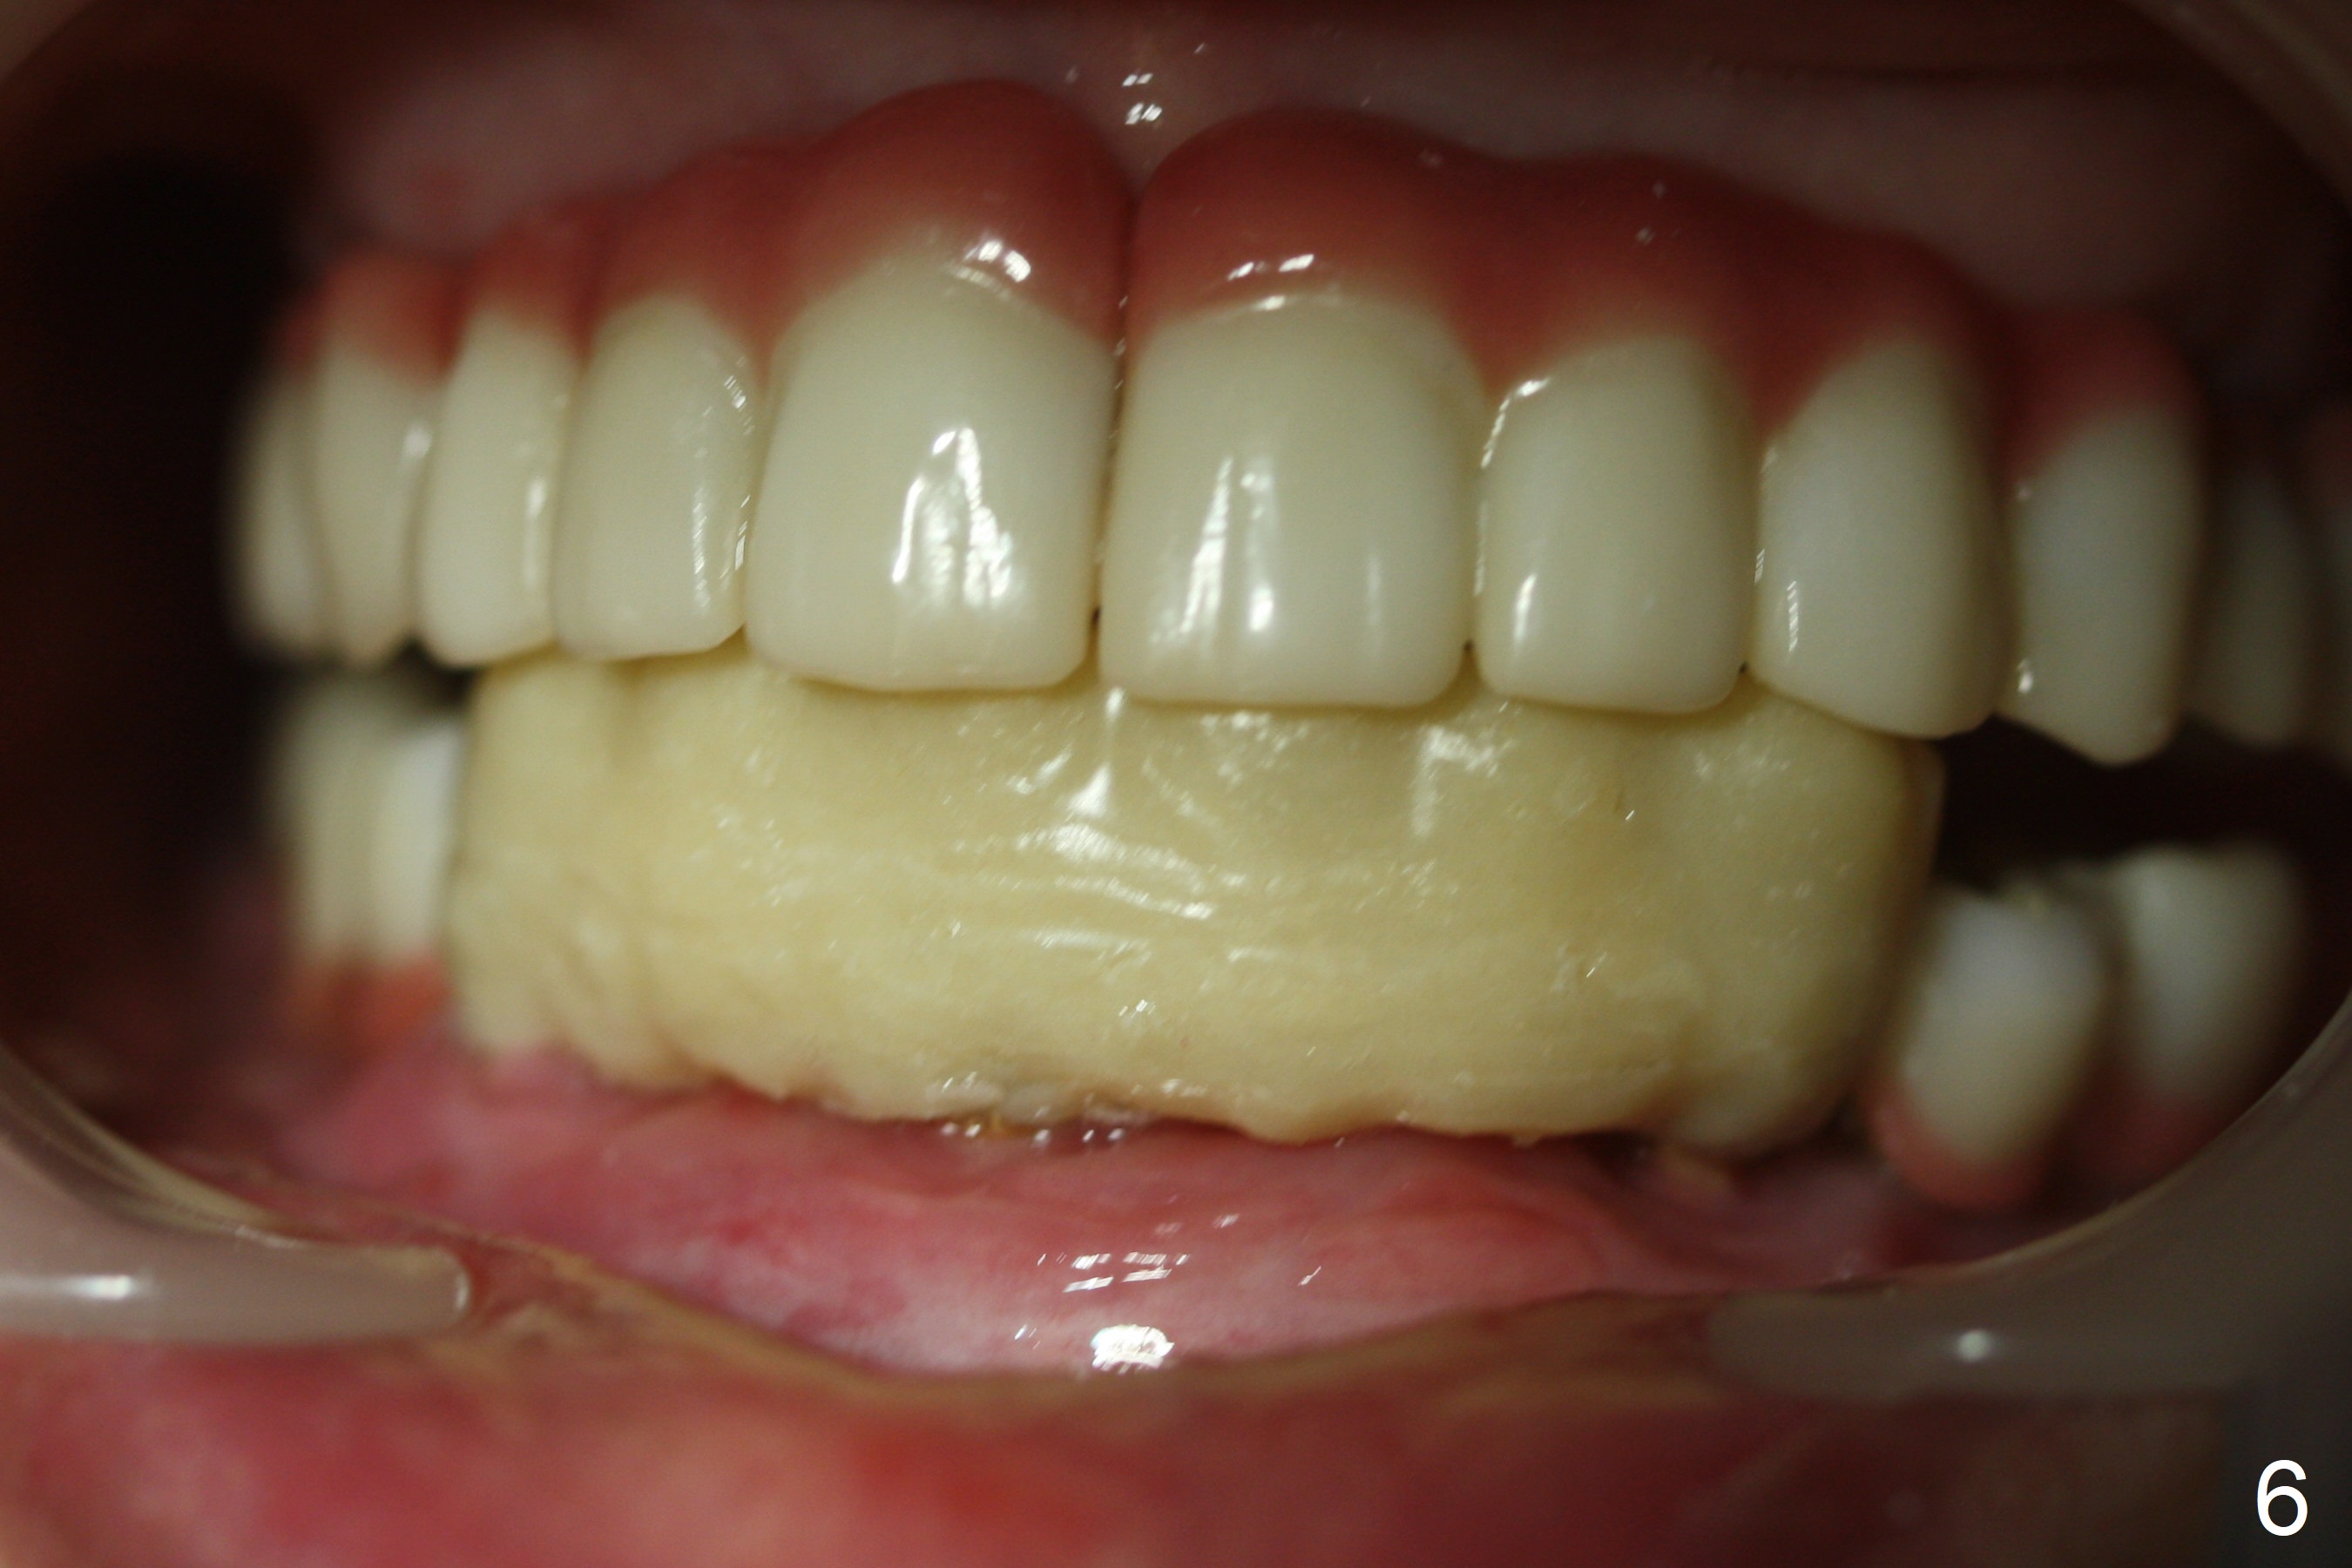

A 56-year-old woman with atrophic jaws requests redoing lower implant restoration (in function 1 year) for cosmetic reason and placing an implant at #19 (because she could not masticate on the left). Note the discrepancy between CR and CO (Fig.1,2). There is gingival hypertrophy at #31 (Fig.3), while the anterior restoration looks short with gingival recession (Fig.4). The patient is pleased instantly when lower anterior provisional is fabricated (Fig.5-7).